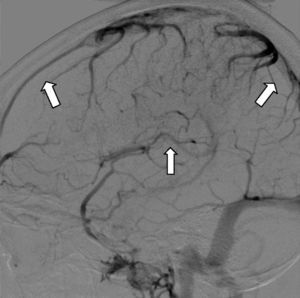

Hoy en día la angiografía por sustracción digital (ASD) se realiza raramente para el diagnóstico de TVC. Es de utilidad en casos de trombosis de venas corticales en los que los estudios de imagen no invasivos son no concluyentes. Es útil también para descartar la presencia de una fístula dural o en los casos en los que se planea un tratamiento endovascular trombolítico químico o mecánico34 (fig. 6).